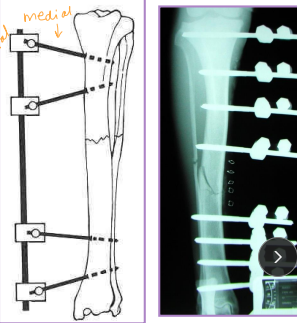

External Skeletal Fixation

Why: Long bone fractures, Arthrodesis, Spinal stabilization, Mandibular fractures, Distraction osteogenesis

What: Pins, Clamps, Connecting bar

Use threaded pins, Lg size possible (25% diameter of bone)

How: use the simplest frame design that will work

Place 3-4 pins per main fragment, evenly, and perpendicular to long axis of bone along safe corridors

Safe corridors: distal radius/ulna, tibia/fibula

Femur has NONE

Connecting bar placed 1-2 cm from bone

Clamp interface inside connecting bar

Types of External Skeletal Fixation

What:

Pins: Engage bone, provide stabilization

Clamps: Secure pins to connecting bar.

Connecting bar: Links clamps and pins.

Types:

Linear: Frame strength ↑ with complexity

Type IA: Unilateral, uniplanar

Type IB: Unilateral, biplanar

Type II: Bilateral, uniplanar

Type III: Bilateral, biplanar

Linear Type 1/A ESF

½ pins

Unilateral, uniplanar

all pins enter one 1 side

all pins going in the same plane (medial→lateral)